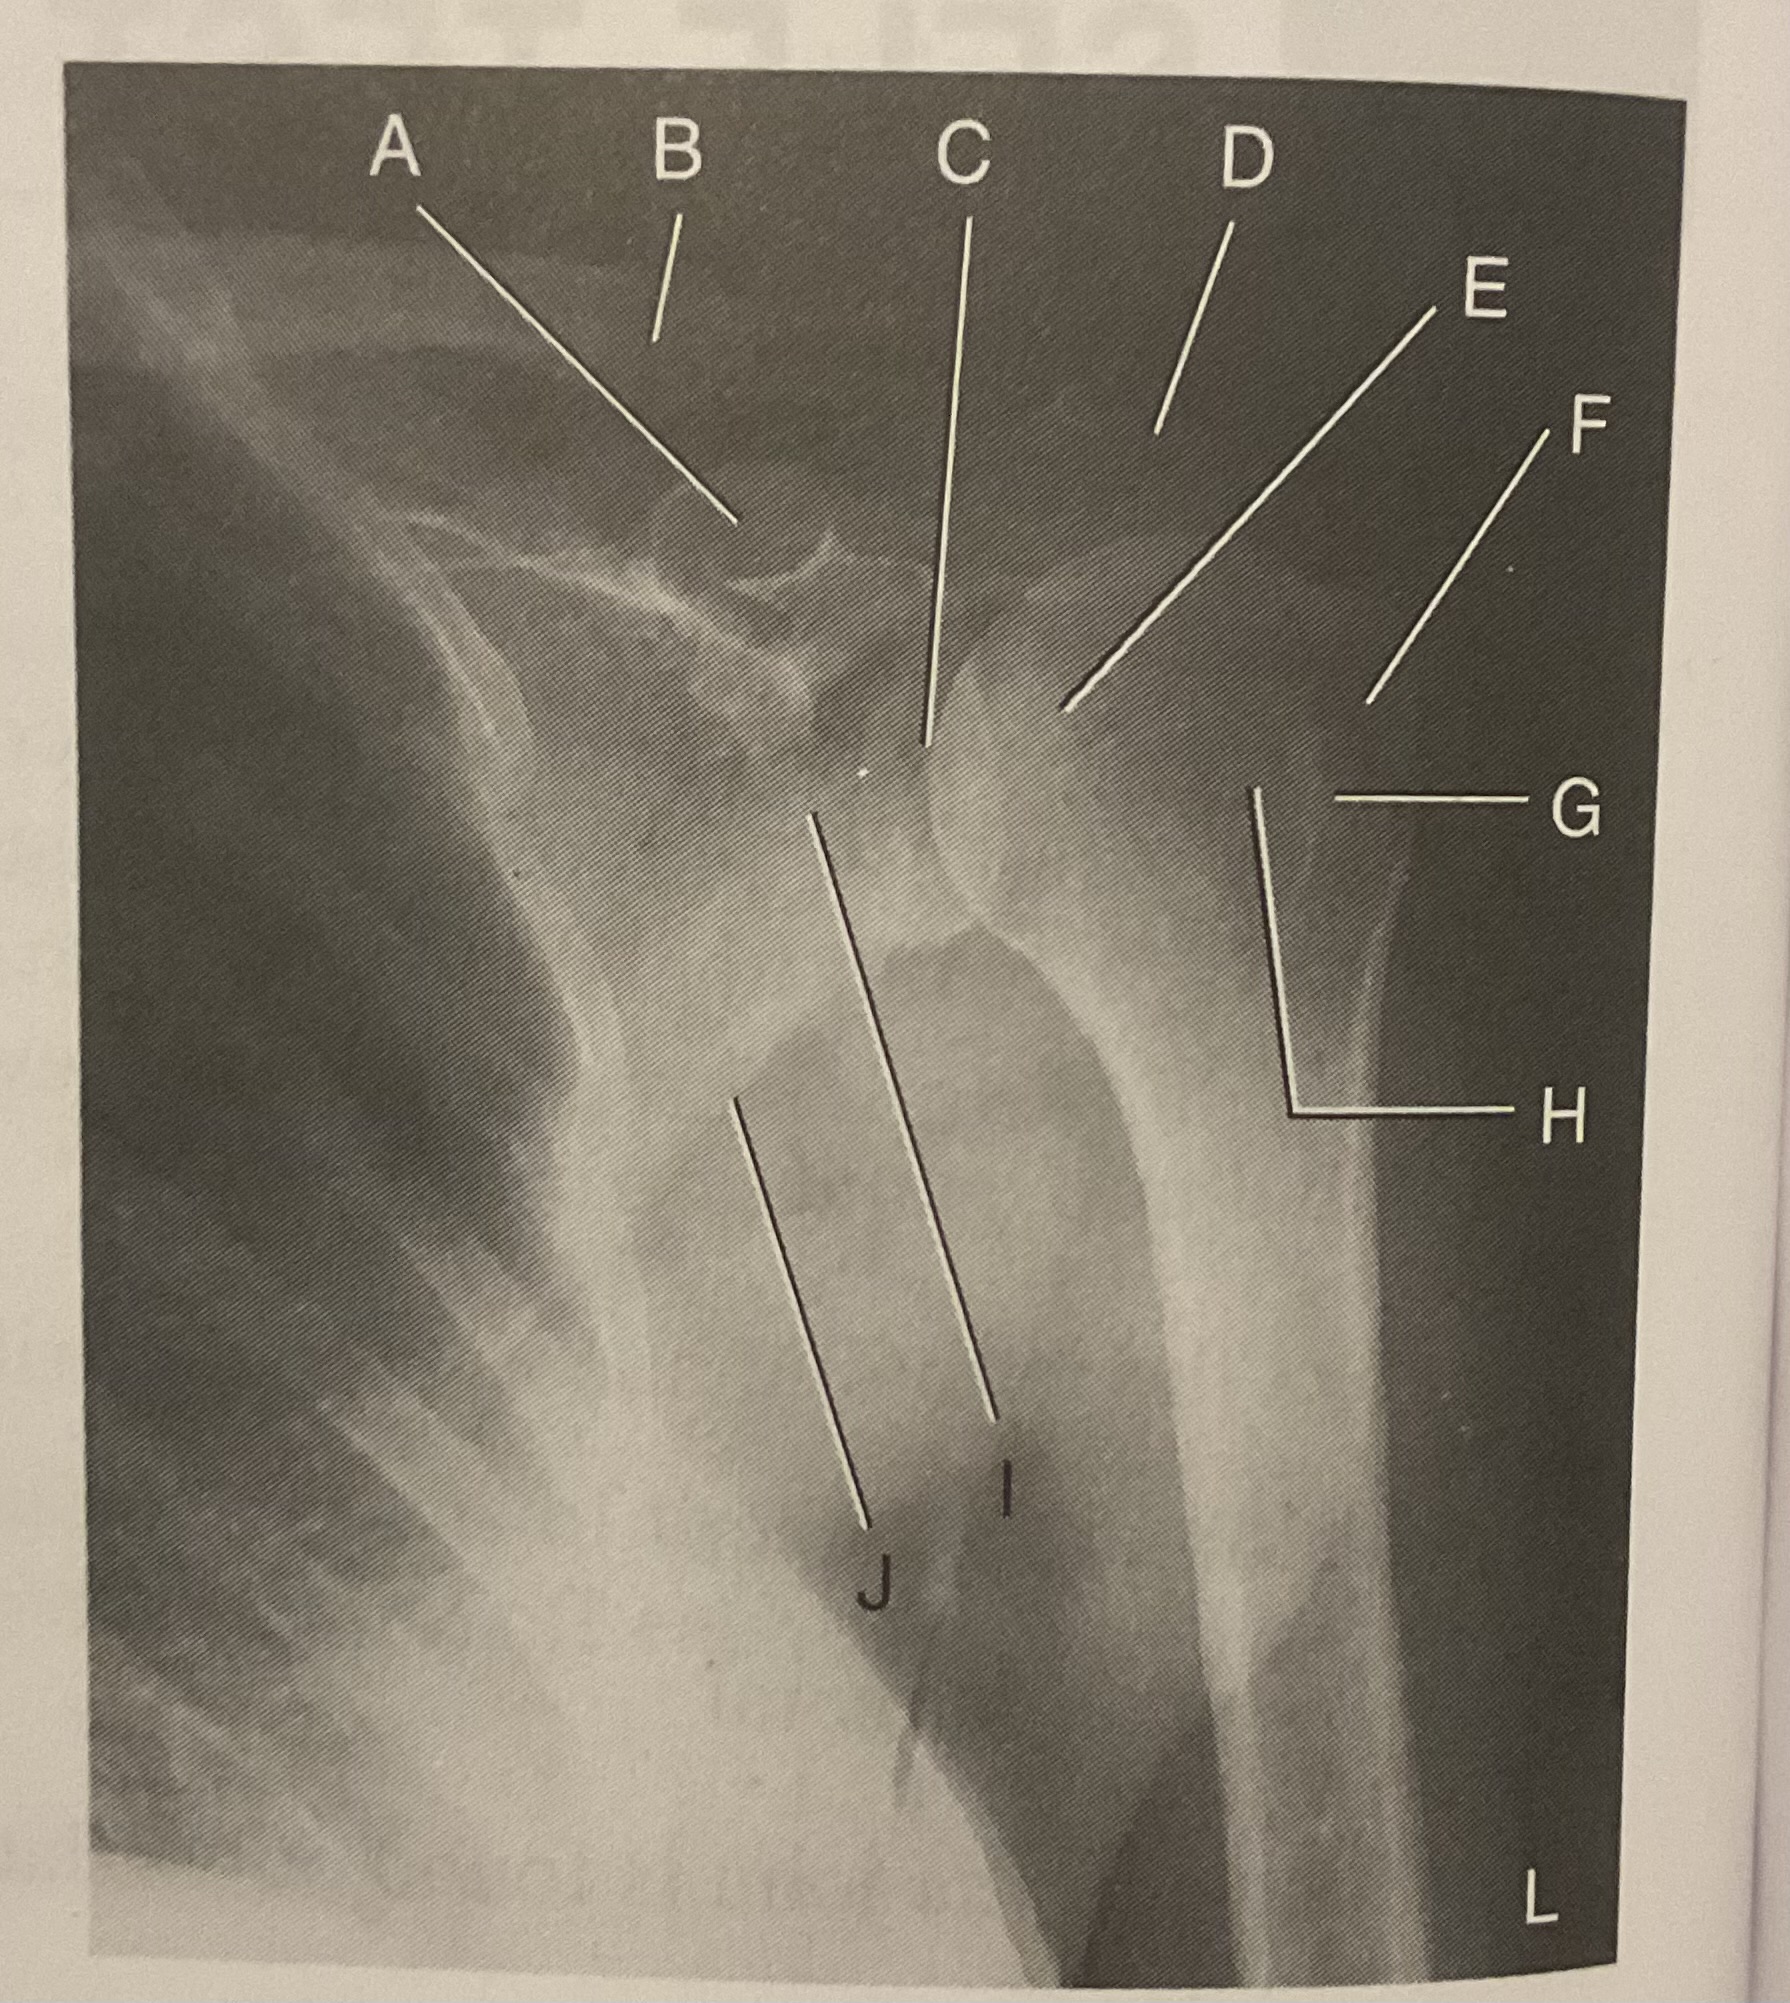

A?

Coracoid process

B?

Clavicle

C?

Scapulohumeral joint

D?

Acromion of scapula

E?

Head of humerus

F?

Greater tubercle

G?

Intertubercular sulcus

H?

Lesser tubercle

I?

Neck of scapula

J?

Lateral (axillary) border of scapula

What AP projection does this image represent?

External